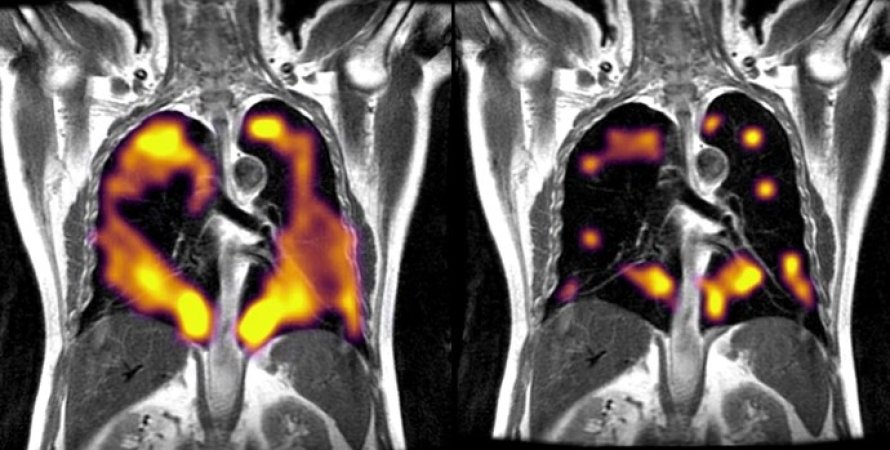

Во время сканирования пациент вдыхает ксенон, что позволяет увидеть структуру и вентиляцию легких | Фото: University of Oxford Department of Oncology

Медики использовали новый вид технологии визуализации, называемый "МРТ с гиперполяризованным ксеноном" (129Xe МРТ). Технология дает возможность получить очень подробные сведения о работе легких и передаче кислорода в кровь.

"МРТ 129Xe выявляет те части легких, где физиология поглощения кислорода нарушена из-за длительного воздействия COVID-19 на легкие", — говорит Джим Уайлд, руководитель отдела визуализации в Университете Шеффилда, Великобритания.

"Наше сканирование с использованием МРТ с гиперполяризованным ксеноном показало, что аномалии, которые обычно не видны при привычных сканированиях, действительно присутствуют, и эти аномалии препятствуют попаданию кислорода в кровь, как это должно происходить во всех частях легких", — говорит радиолог Фергус Глисон, участник исследовательской группы.